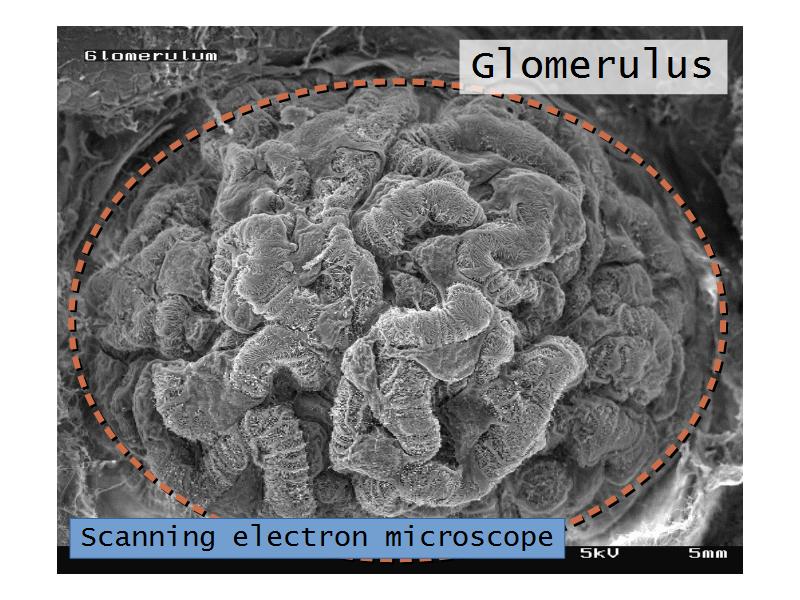

- Structure of the nephron and collecting tubules

- The renal corpuscle

- Complete the drawings for each slide in the practical workbook.